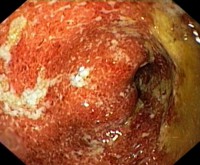

Колоректальный рак и язвенный колит

У пациента с хроническим язвенным колитом возникает ...23.12.18

Краткий обзор рака мочевого пузыря

РМП - это одна из распространенных злокачественных опухолей